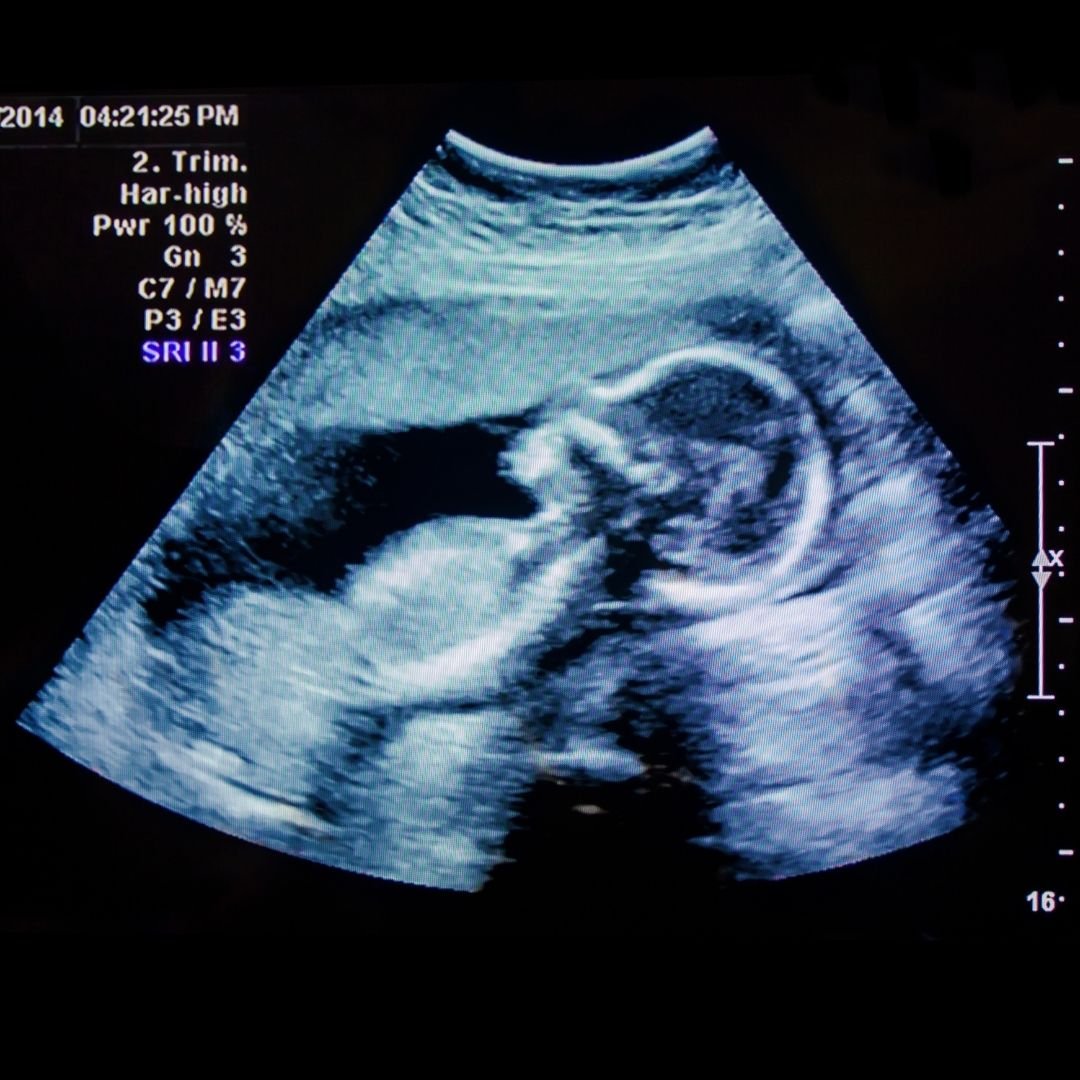

Our team of OB GYN consultants is committed to ensuring every visit is comfortable, informative and personalized with a focus on women’s health and wellness care.